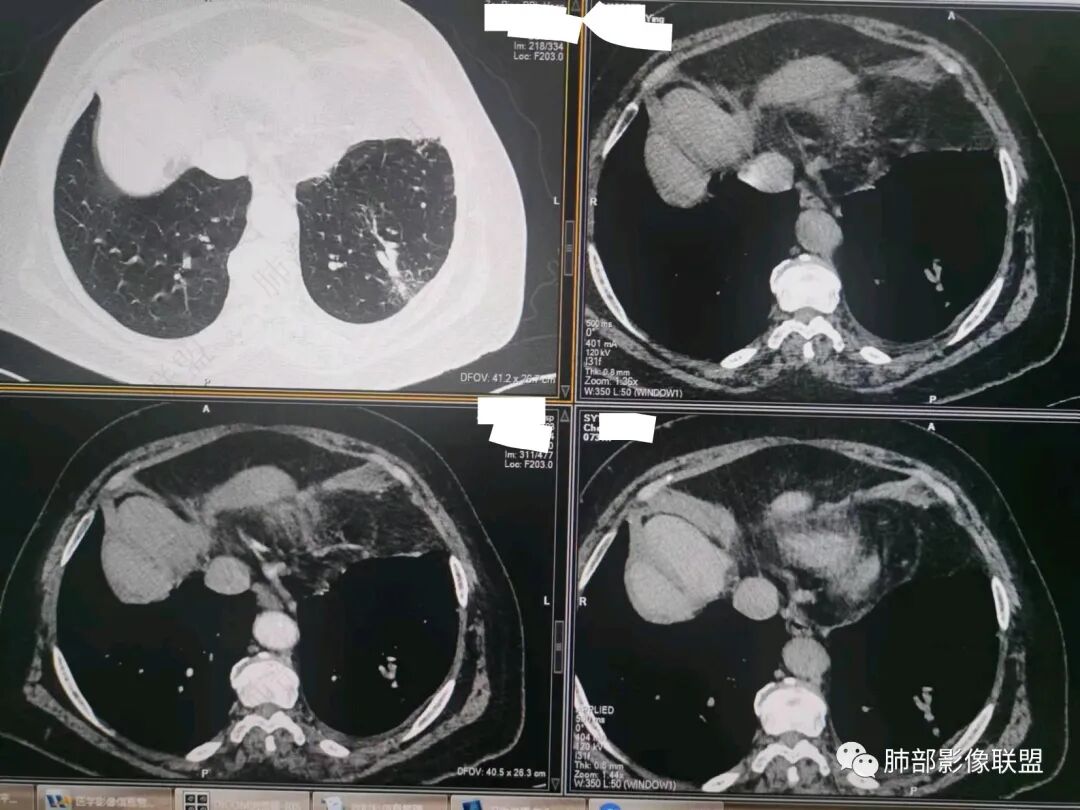

南边:今天的病例肺内部分基本都是炎性特点,问题就在于胸膜。

糊墙:肺内病灶不侵犯壁层胸膜或以外,与壁层胸膜相对而言分界清楚。

栽赃:病灶侵入壁层胸膜及胸膜外脂肪间隙、胸壁其他结构等,相对在病灶中央区域,与胸膜分界不清。

南边:看肺内病灶与胸膜分界清,增强后强化不一致,需要综合分析。

这是糊墙。

这就栽赃。都突到外面去了。

看看这个,骨头都侵袭了。

今天的病例有些伪影。

看起来就觉得放射状伪影。

我就不知道这些是胸水,伪影导致密度增高?还是胸膜增厚?

我只是邓较瘦:今天平扫的像栽赃, 增强感觉是增厚的胸膜。

南边:一般这类侵袭,是中央地带毛刷状延伸到胸膜内。

而且旁边这么宽的少,所以觉得很奇怪,不太符合,我是怀疑与照片有关。

你对比一下两侧的密度。肌肉密度不一样。

我只是邓较瘦:南大这个我感觉局部似乎是栽赃呢 箭头那里是啥?

南边:栽赃是这样过去的,中间不会脂肪间隙清晰。

胸壁的组织,除非你怀疑胸壁转移结节。

转移淋巴结。

局部侵犯。有差异。

我只是邓较瘦:这个是侵犯出去不是淋巴结吧?

南边:不是,你看看强化与淋巴结不一致。

我只是邓较瘦:强化与肿瘤差不多。

南边:是。